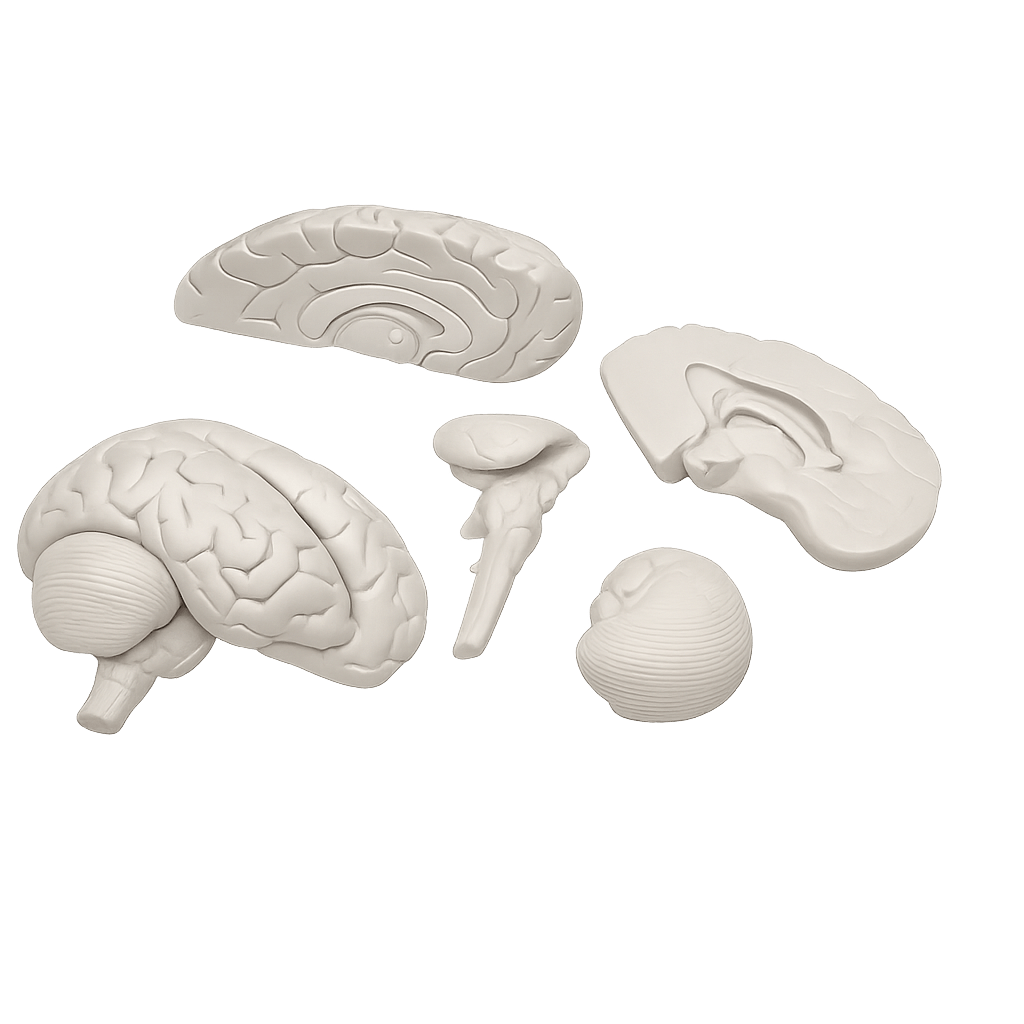

Erler-Zimmer

Anatomisches Gehirnmodell, lebensgroß, 5-teilig

Artikelnummer: SKU: EZC918

PZN: PZN:

Packaging unit: VE:

Auf Lager: In 1–3 Werktagen geliefert

★★★★★ 0 Bewertungen112,90 €112,90 €112,90 € -